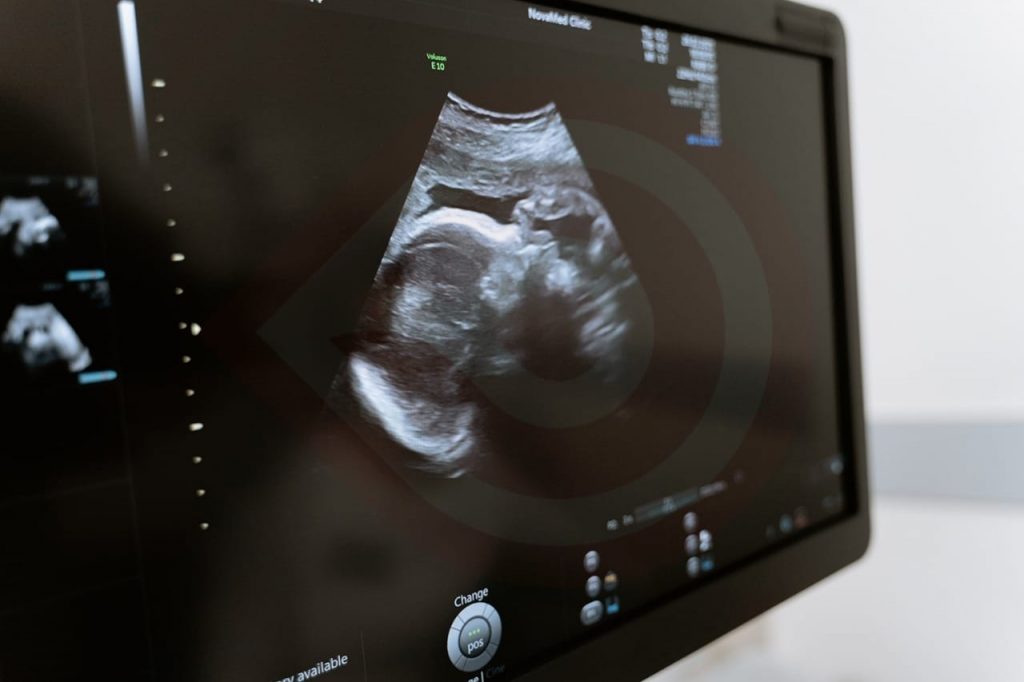

Ciudad de México. – Derivado de que más de 60 por ciento de malformaciones congénitas son de origen desconocido, el Instituto de Seguridad y Servicios Sociales de los Trabajadores del Estado (Issste) promueve en las mujeres embarazadas medidas preventivas con evidencia científica para reducir algunos riesgos, como la prescripción de ácido fólico y vitamina B durante la gestación, que ha demostrado eficacia para prevenir alteraciones del desarrollo del tubo neural, es decir, del sistema nervioso central, informó el director general, Pedro Zenteno Santaella.

El especialista adscrito a la Unidad de Cuidados Intensivos Neonatales (UCIN), del Centro Médico Nacional (CMN) “20 de Noviembre”, Armando Torres Rodríguez, precisó que en 2021, 45 por ciento de los ingresos a la UCIN fueron pacientes con algún tipo de malformación. “Al ser un hospital de referencia de alta especialidad, la malformación más frecuente que atendemos es la cardiaca, alteraciones estructurales que no llevaron el adecuado desarrollo de ese corazón; afecciones cromosómicas como la trisomia 21 vinculada al síndrome de Down, ocupan el segundo lugar; seguidas por alteraciones de extremidades y las de tipo gastrointestinal”.

Explicó que una malformación congénita es una falta de desarrollo habitual o normal de un órgano durante la gestación, que va a repercutir en el aspecto estético, funcional y en ocasiones alterar el desarrollo del recién nacido.

Torres Rodríguez señaló que aproximadamente en 60 por ciento de los casos no se conoce la causa de la malformación y en 40 por ciento se identifican otros posibles orígenes atribuibles al feto, como las alteraciones cromosómicas; el relacionado a patologías de la madre en el embarazo, como diabetes, o infecciones por rubeola, varicela y zika.